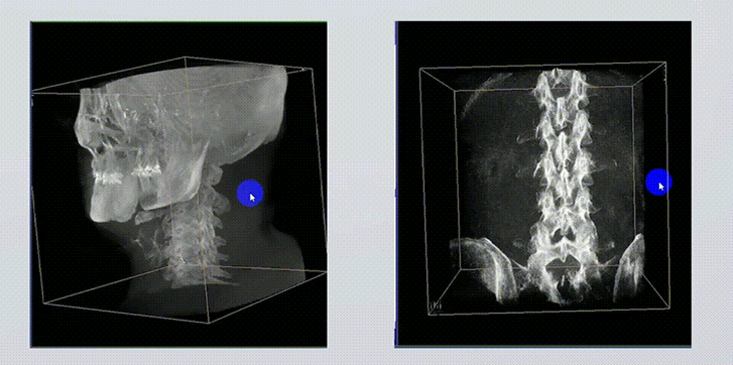

1、術(shù)中實(shí)時(shí)三維成像

術(shù)中三維成像和橫斷面圖像提供多角度的手術(shù)診斷信息,輔助醫(yī)生進(jìn)行術(shù)中評估判斷,諸如骨折復(fù)位情況和內(nèi)植入螺釘?shù)某叽绾臀恢?,輔助手術(shù)更好地完成。

2、三維成像視野大

提供更大的術(shù)中三維成像視野,采集更多圖像信息,可一次拍全全段頸椎、全段腰椎、七節(jié)胸椎、雙側(cè)骶髂關(guān)節(jié)、股骨頭及單側(cè)盆骨。